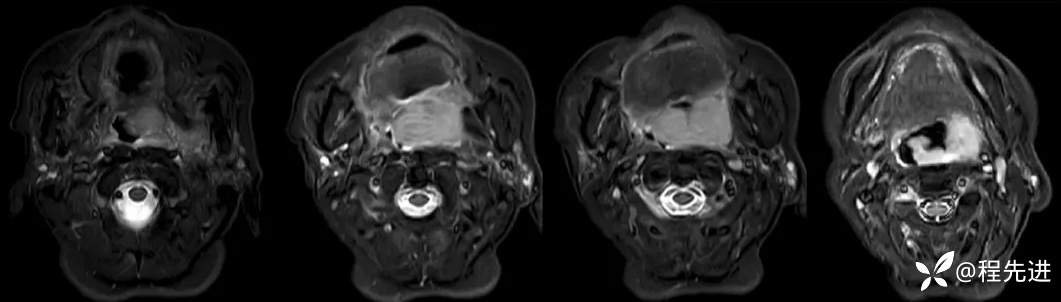

MRI平扫+增强:

T2:

T2压脂: